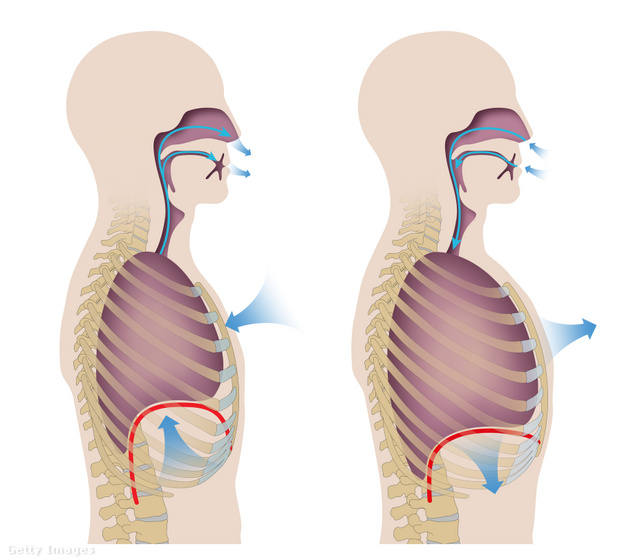

A gyakorlat alappillérei a szakember magyarázatával

- Rekeszizom: A légzés legfontosabb résztvevője a rekeszizom. Hiába lenne akkora a tüdőnk, mint egy bálnának, ha nincs rekeszizmunk, nem tudnánk lélegezni. Belégzéskor lefelé mozdul, kilégzéskor pedig fölfelé mozog, megszűntetve a nyomást. Ezért kell a gyakorlatsort kilégzés után elvégezni, mert a hasi nyomás ilyenkor csökken, a rekeszizom felfelé mozdul.

- Az Uddiyana Bandha: Akik jógáznak, azoknak nem ismeretlenek a Bandhák, azaz az energetikai zárak. A jóga 3 Bandhát különböztet meg, de minket most csak az Uddiyana Bandha, azaz a hasi zár érdekel. Jelentése: repülni, felemelkedni. A rekeszizmot a mellkas irányába „felemeljük”, ugyanakkor a belső hasi szerveket a hátgerinc irányába mozdítjuk el. Azaz: kilélegzünk, és befelé/felfelé szippantjuk az alhasat.

- Légzés: 2 ütemen keresztül, orron át lélegzünk be, 4 ütemen keresztül lélegzünk ki a szájon át. 3 kört csinálunk ebből, az utolsó körnél, a kilégzés után kinn tartjuk a levegőt, nyitjuk a mellkast és beszippantjuk a hasat. 4-5 másodpercig rögzítjük ezt a testtartást. Utána még 2 kört végzünk el. Majd folytatjuk a következő testtartással. A légzés kinntartását 15-25 másodpercig kell növelni. Heti 2 gyakorlással (25-30 perc a gyakorlatsor elvégzése) 3-4 hónap alatt fantasztikus eredményeket lehet elérni - ismerteti a lehetséges eredményeket a szakember.